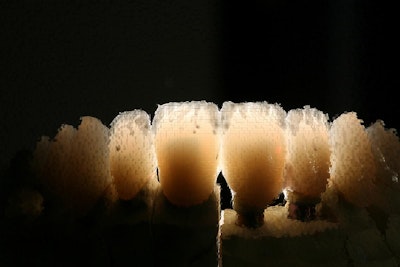

It’s different with intraoral photos, of course. That’s all about showing a restoration’s intricacies and fine details.

“I want to show how meticulously designed the restorations are,” Dr. Seay said. “It’s those little nuances that make it more interesting, the craftmanship.”